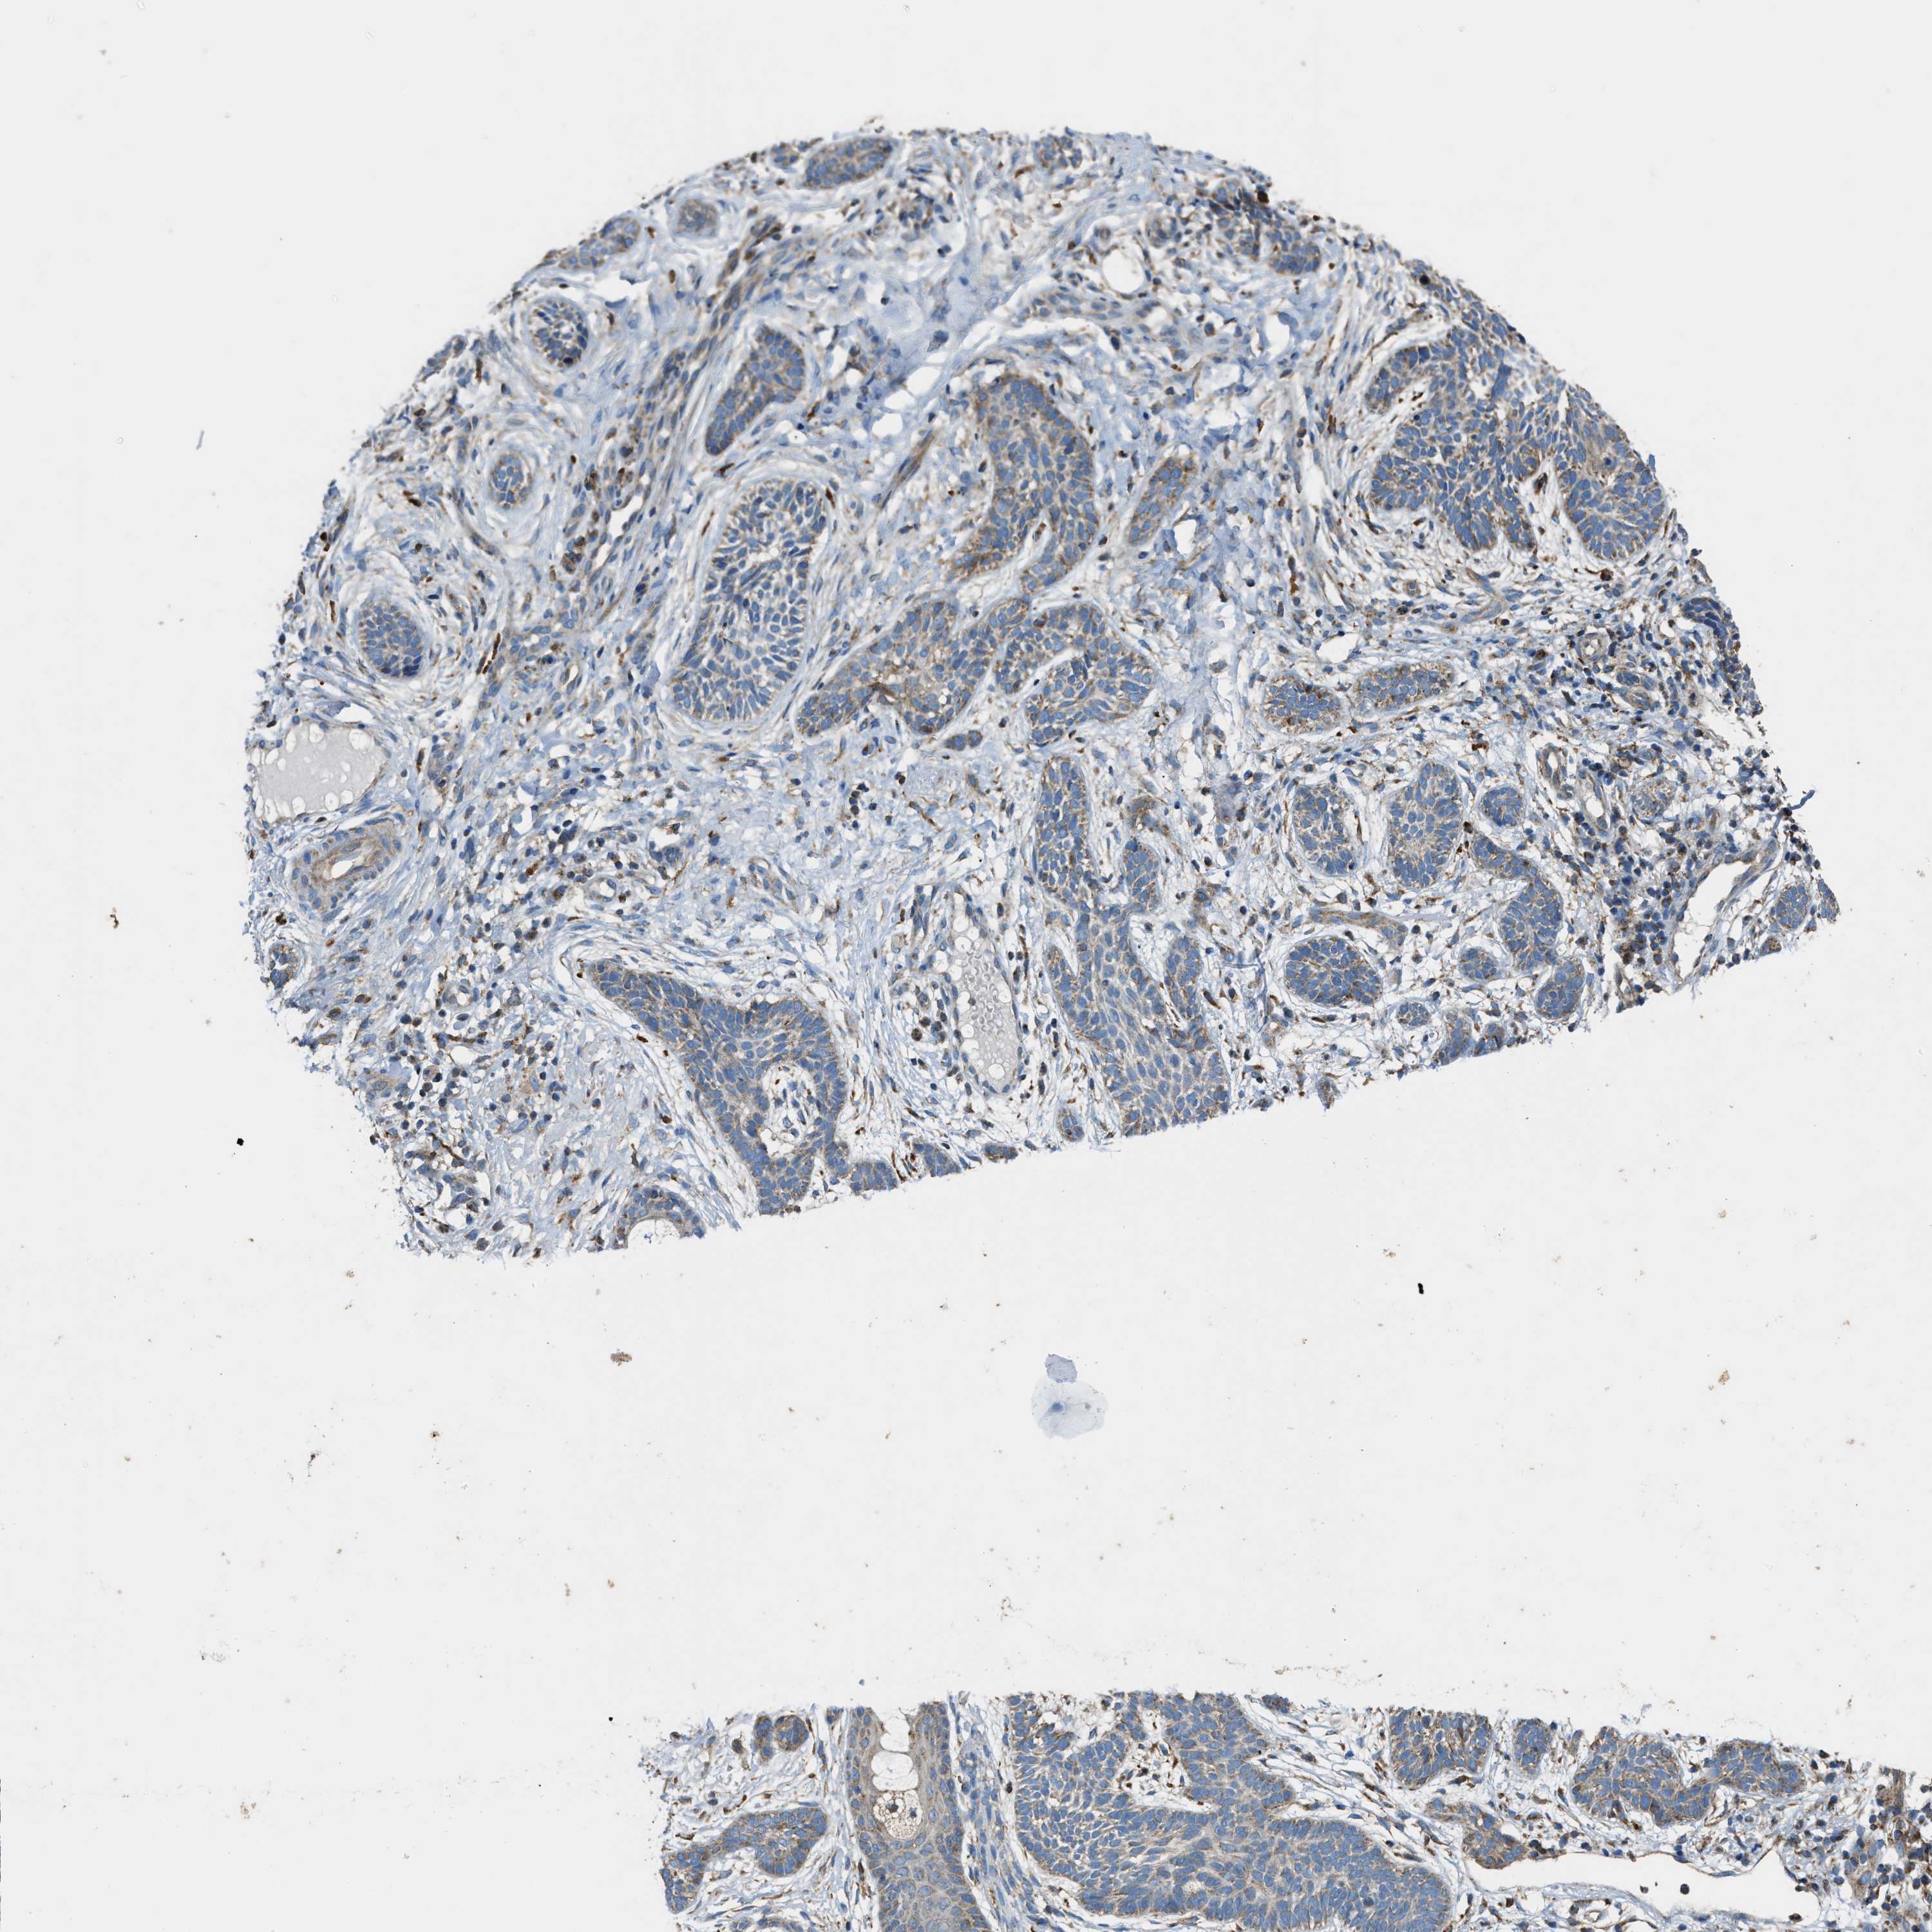

Basal cell and squamous cell cancer

SKIN CANCER - Protein expressioni

A mouse-over function shows sample information and annotation data. Click on an image to view it in a full screen mode. Samples can be filtered based on level of antibody staining by selecting one or several of the following categories: high, medium, low and not detected. The assay and annotation is described here.

Antibody stainingi

Antibody staining in the annotated cell types in the current human tissue is reported as not detected, low, medium, or high, based on conventional immunohistochemistry profiling in selected tissues. This score is based on the combination of the staining intensity and fraction of stained cells.

Each image is clickable and will lead to virtual microscopy that enables deeper exploration of all samples and also displays staining intensity scores, fraction scores and subcellular localization as well as patient and tissue information for each sample.

Antibody HPA021167

Staining

High

Medium

Low

Not detected

Intensity

Strong

Moderate

Weak

Negative

Quantity

>75%

75%-25%

<25%

None

Location

Nuclear

Cytoplasmic/membranous

Cytoplasmic/membranous,nuclear

Basal cell carcinoma